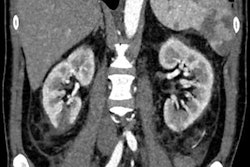

All images were acquired in the supine position on an Ingenuity Elite CT scanner (Philips Healthcare) without contrast. Using coronal CT images obtained from different cross-sections in these patients, the researchers produced a dataset of 1,799 images, which consisted of 790 images for patients with kidney stones and 1,009 of clinically normal subjects. A radiologist and a urologist separately evaluated the images and labeled them as either having kidney stones or no kidney stones.

The authors noted that the algorithm performed well even on small kidney stones. In addition to identifying the presence of kidney stones, the algorithm also successfully marked the areas of interest it used during its decision-making process, according to the researchers.

"Clinically, the regions identified by the model [were] in agreement by our medical experts for most of the images," they wrote. "Hence, our proposed [deep-learning] model is accurate and can assist the radiologists to detect kidney stone cases accurately."